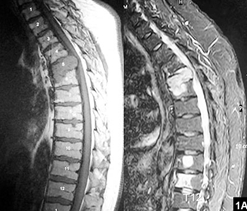

脊椎的放射治療,多用於紓緩性治療,一般來說,電療的次數較少、治療期較短,故所產生的副作用相對不及根治性電療明顯